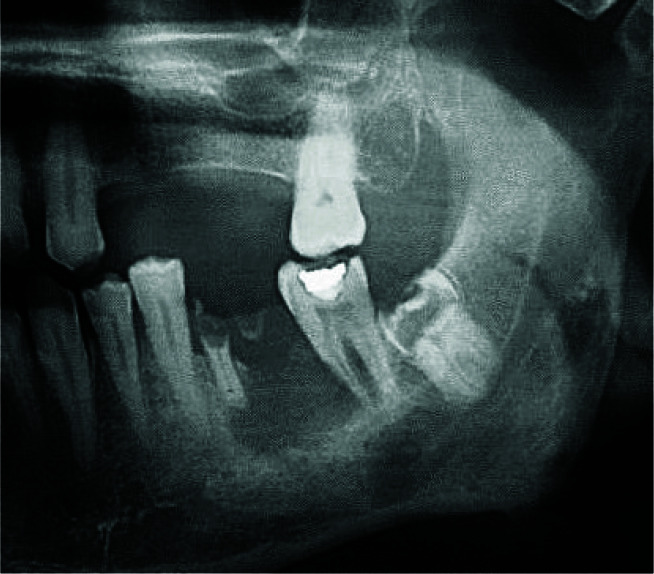

Metastatic lesions of the jaws are a diagnostic challenge because of their scarcity and uncharacteristic clinical-radiographic features. Carcinoma of unknown primary origin (CUP) is characterized by the existence of metastatic disease with no recognized primary neoplasm after a comprehensive work-up. CUP shows a poor prognosis with limited treatment choices. This paper presents a 64-year-old male with a chief complaint of paresthesia of the chin and lower lip. Panoramic radiography showed an ill-defined radiolucency in the left mandibular molar area and the residue of the first molar root. Microscopic examination demonstrated features of mucin-producing adenocarcinoma and was not similar to common neoplasms of the jaw. The whole-body scan revealed multiple osseous uptakes. CDX2 was diffusely positive. However, in the end, the origin of the primary tumor was not determined. Considering the aforementioned data, the diagnosis of metastatic adenocarcinoma with unknown primary origin was made. CUP of the oral cavity is an extremely rare event. The possibility of metastasis should be raised in a patient who complains of paresthesia. Awareness of the clinical and histopathologic features of these malignancies is crucial for clinicians and pathologists to have a proper diagnosis.